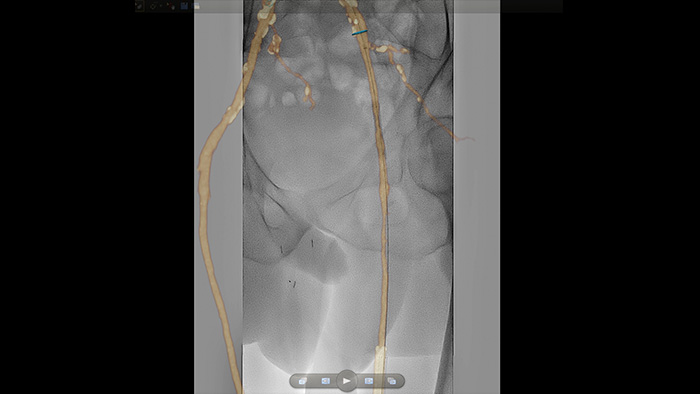

SmartCT Roadmap overlays a 3D reconstruction using SmartCT Angio or SmartCT Soft Tissue, to emphasise target vessel and lesions, aiding guidewire and catheter navigation through complex vessel structures. All controlled via the touch screen at the table.